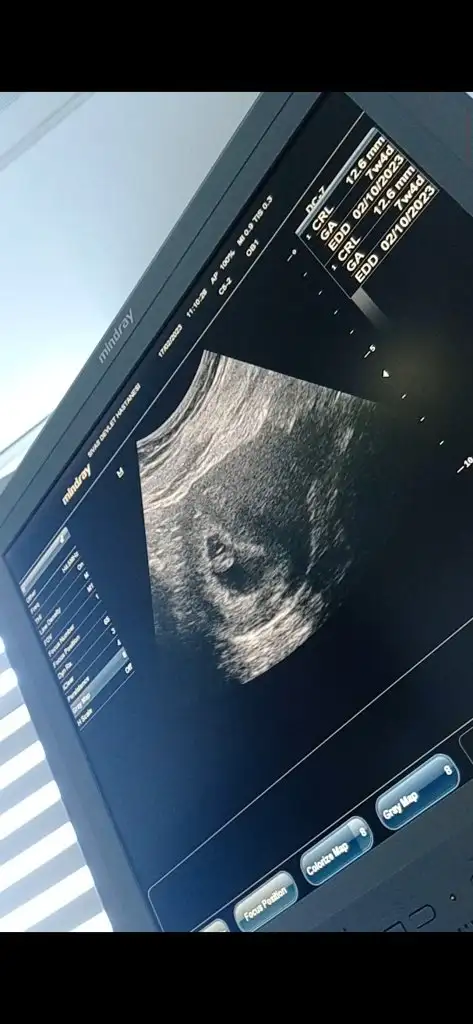

Merhabaaaa, 7+5 tahmin alabilir miyimmm karından ultrason